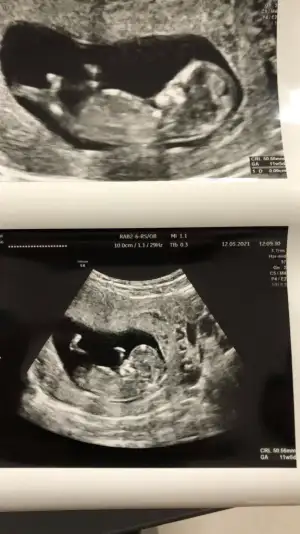

Ikra meyra Ikra meyra merhabaaa Canım :) Arkadaşımın bebisinin fotosunu atiyorum.Sana zahmet tahminde bulunabilirsen çoooook sevinirim :) Şu an 12+2 :)

• IMG-20210517-WA0002.webp

• IMG-20210517-WA0001.webp

• IMG-20210517-WA0000.webp